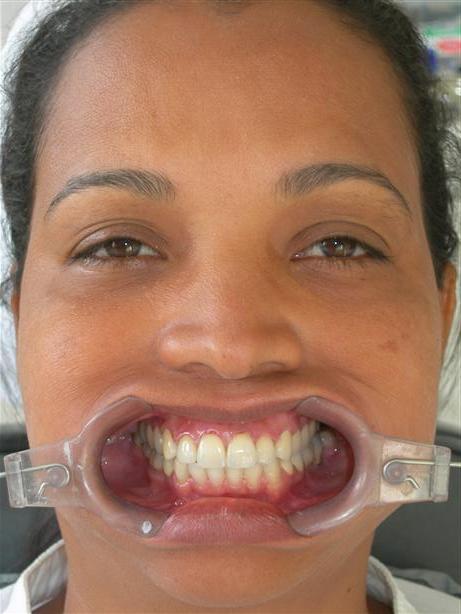

Caso concluído com próteses

metalocerâmicas cimentadas

Caso concluído com próteses metalocerâmicas cimentadas